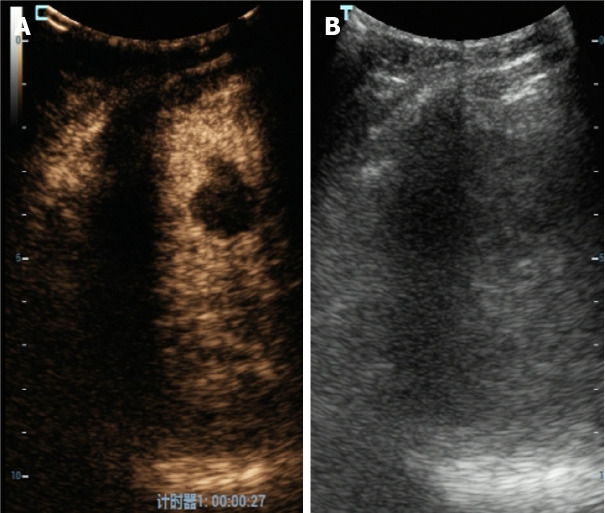

Abstract Image